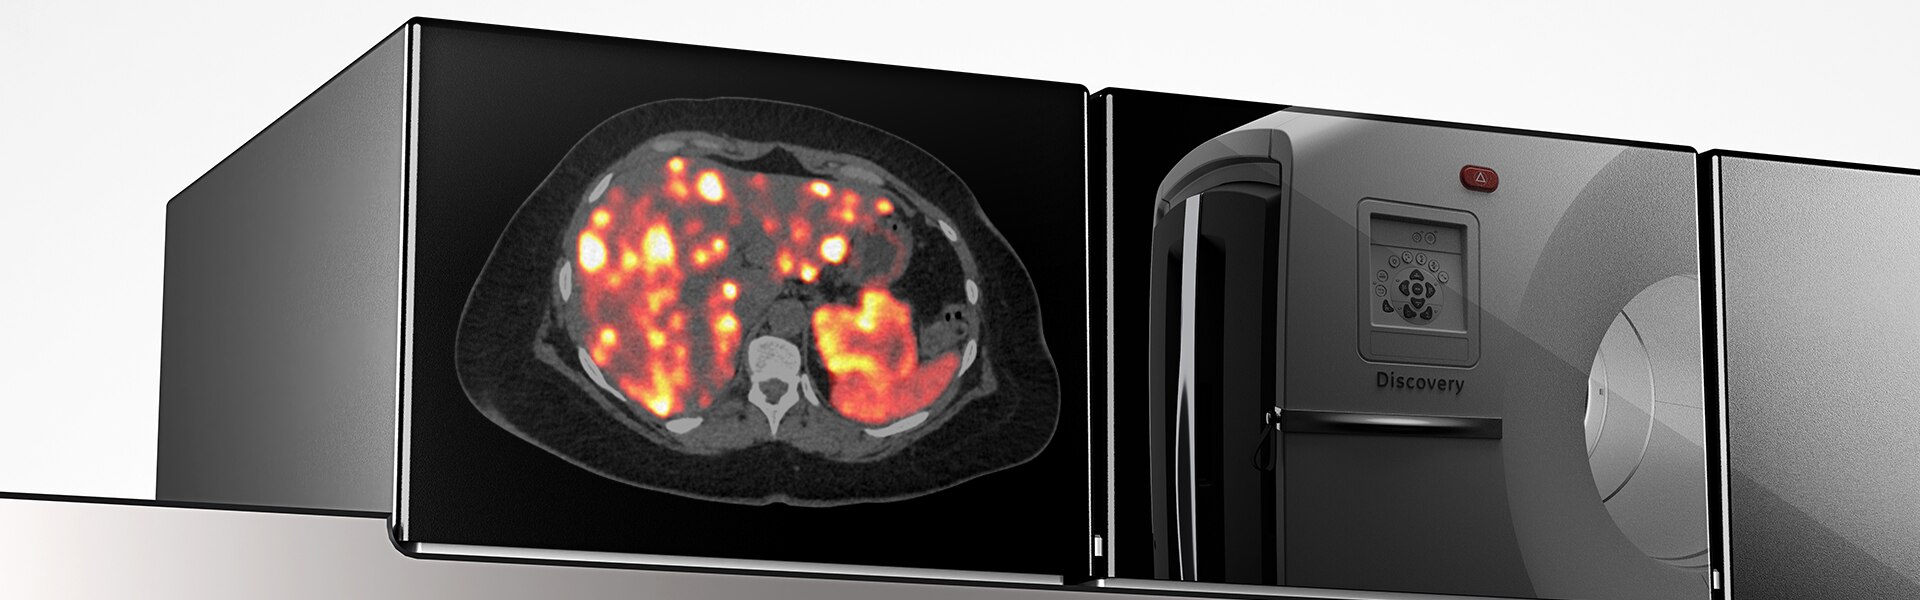

Imagens Clínicas

Várias lesões pequenas nas pernas e ao longo do pescoço.

A lesão da orelha direita mede na TC 3,5 mm. Tumor no quadril comendo o osso.

Cervical direito medindo 6 mm.

Acne visto nas costas.

Pulmão direito, virilha direita e tumor atrás do joelho direito.

Câncer na cabeça e pescoço.

Pós-radioterapia, progresso do câncer. Pequeno câncer de mama.

Linfonodos ávidos por FDG na axila esquerda (vacinação contra COVID-19).